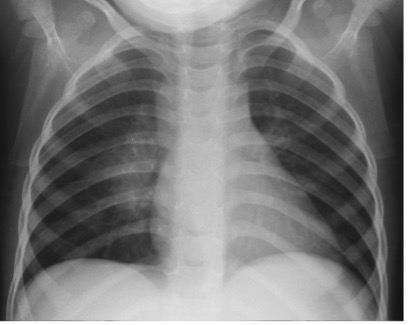

Chest X-Rays (CXR) play a pivotal role within these diagnostic algorithms, and so the interpretation of CXRs is now more relevant than ever in the fight against child TB.

That is why we are excited to inform you about a new FREE online course launched by The Union which can strengthen your team’s capabilities in child tuberculosis diagnosis: Interpretation of CXRs in Children with Presumptive TB

Based on our Diagnostic CXR Atlas for Tuberculosis in Children: a Guide to Chest X-ray Interpretation (2nd edition, 2022), this course is designed to provide pragmatic guidance to healthcare professionals like you who work tirelessly to combat child tuberculosis in high-burden settings.